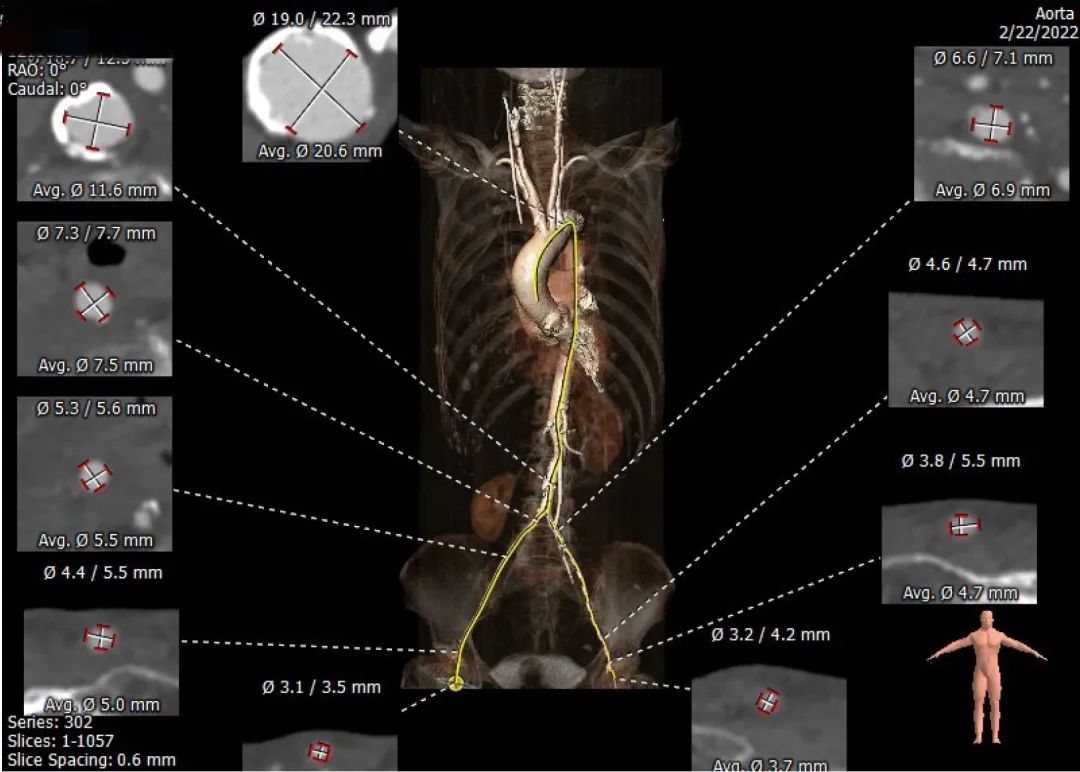

次日,完善CT影像评估,提示双侧股动脉入路血管极细,右侧入路最窄处仅5.0mm,左侧最窄处仅4.7mm。经过综合评估,手术团队计划全麻下,经右侧股动脉入路,选用直径仅14F的Commander输送系统,植入SAPIEN 3 23mm瓣膜,标准体积释放,并根据超声评估决定是否进行后扩。

Annulus area 390mm²,Min/Max 21mm/23mm,Area Derived 22.3mm;LVOT area 384mm²,Min/Max 20.7 mm/24.5 mm,Area Derived 22.1mm。

三叶瓣,NCC窦底钙化较重,瓣叶较长。

SOV 32.6×33.6mm,STJ 30.3mm,RCA 15.5mm,LCA 11mm;窦部宽大,STJ直径较宽,瓣叶冗长,提示冠脉闭塞低风险。

右侧股动脉入路平均直径5.5mm,左侧入路内径4.7mm。